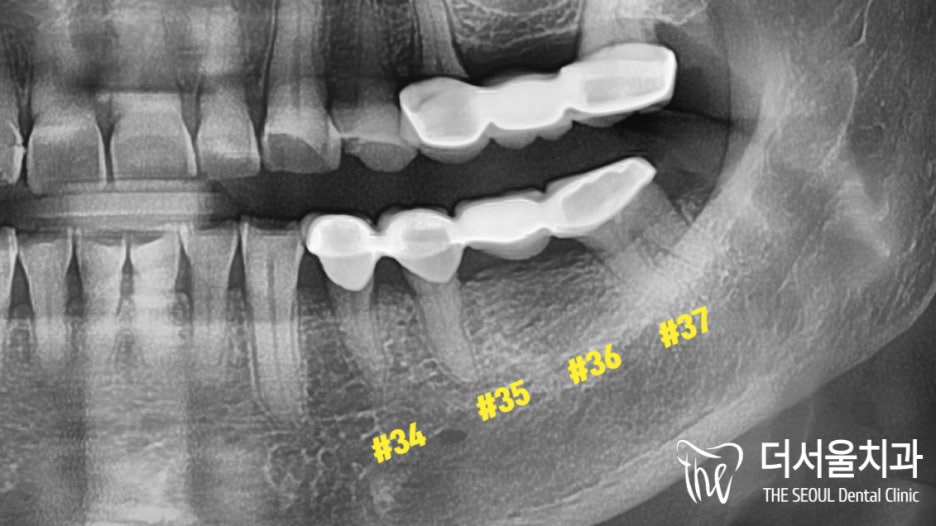

자, 본론으로 들어가

브릿지가 올려져 있는 곳을 확인했습니다.

생각보다 꽤 많은 양이

깨져 있었는데요.

더서울이 짐작해 본 원인은

오래된 보철 사이에

작은 금(Crack)이 생겨

그 사이로 세균과 외부 이물질이

안쪽에 있는 조직까지

감염시킨 것이죠.

문제가 이차우식으로 이어진 것이고요.

외관도 문제지만 기능적으로

아무런 역할을 하지 못하고 있었기에

빠른 시일 내에

개선을 돕기로 계획을 세웠습니다.